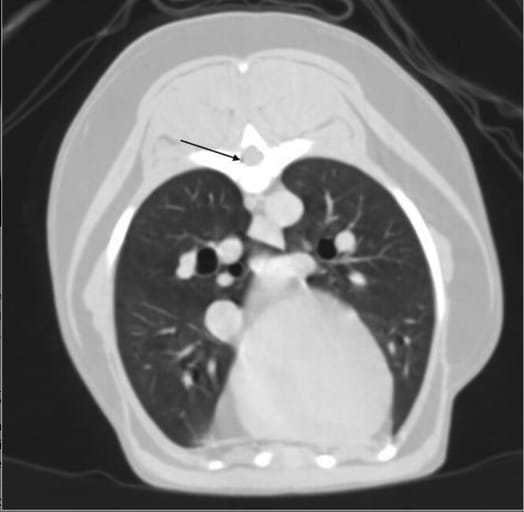

Transverse postcontrast image in lung window of a 9-year-old female spayed mixed-breed dog, presented for hindlimb weakness and lameness. Gas (black arrow) is identified within the right-ventral aspect of the vertebral canal at the level of mid-body T7 vertebral body.

Gas was identified in 66.7% of all cases, with intravascular gas present in 65.5% and extravascular gas in 13.8%. Dogs were more likely than cats to have gas detected (75.0% vs. 58.9%; P = 0.009). Extravascular gas was found in the vertebral canal (8.6%) and fascial planes (6.3%). Intravascular gas was most commonly seen in the subscapular, axillary, and external jugular veins. Postcontrast imaging increased gas detection in dogs but not in cats.